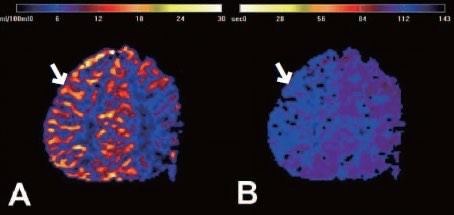

모야모야병은 한 번 협착된 혈관을 약물로 다시 넓히는 것이 불가능하기 때문에, 치료의 기본은 뇌혈류를 새롭게 확보하는 수술적 치료입니다.

수술치료(뇌혈류 재건술, Revascularization surgery)

모야모야병의 핵심 치료는 뇌혈류 공급을 위한 새로운 통로를 만들어주는 수술입니다.

① 직접 우회술(Direct bypass)

• 측두동맥(STA)을 직접 뇌혈관(MCA)과 연결해 혈류를 즉시 공급하는 방식 • 성인에서 가장 많이 시행

• 수술 직후부터 혈류 개선 효과가 빠르게 나타납니다.